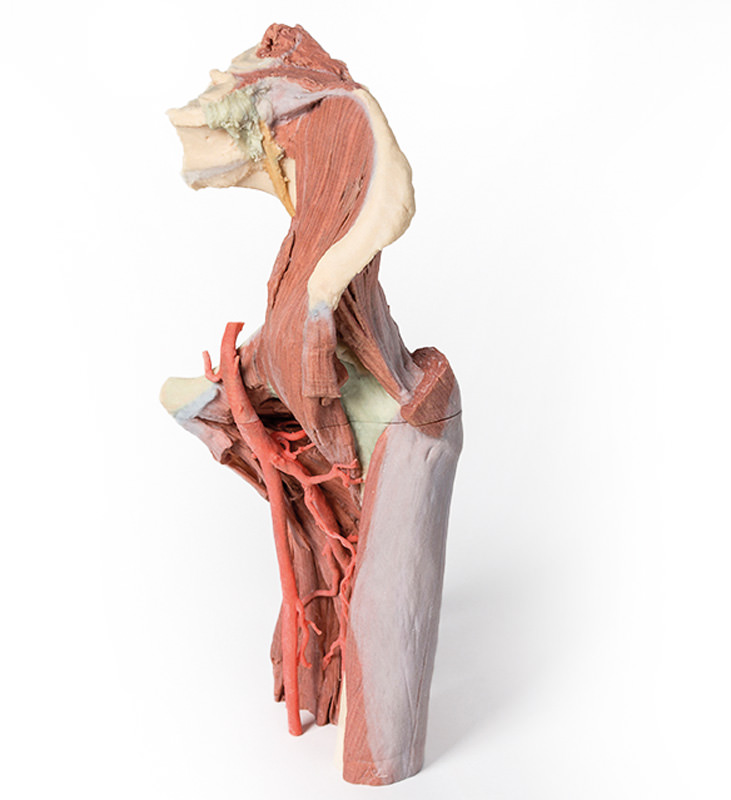

Dieses 3D gedruckte Präparat zeigt eine tiefe Präparation von linkem Becken und Oberschenkel, um den Verlauf der Arteria femoralis und des Nervus ischiadicus von ihrem proximalen Ursprung bis zur Mitte des Femurs zu zeigen. Kranialwärts wurde das Becken entlang der Mittelsagittalebene durchgeschnitten, die Eingeweide des Beckens werden entfernt. Im Becken verläuft der M. coccygeus zwischen Os sacrum und Spina ischiadica, Arteria obturatoria und N. obturatorio treten oberhalb der Membrana obturatoria in das Foramen obturatum ein.